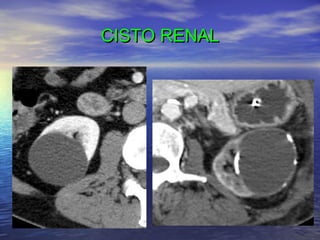

CISTO RENAL

MARSUPIALIZAÇÃO CISTO RENAL